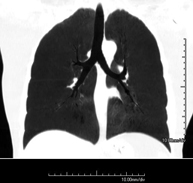

- TC Tórax

Prueba diagnóstica que consiste en obtener imágenes del tórax de alta definición anatómica (pulmones, corazón, mediastino, grandes vasos, caja torácica, etc.) mediante el empleo de un equipo de TC (Tomografía Computarizada). Dichas imágenes se estudian posteriormente en una estación de trabajo que permite reconstrucciones bidimendionales en diferentes planos del espacio y también reconstrucciones 3D (volumétricas). Algunos estudios requieren el empleo de contraste yodado para mejorar la definición de las imágenes. - Angio-TC Aorta torácica